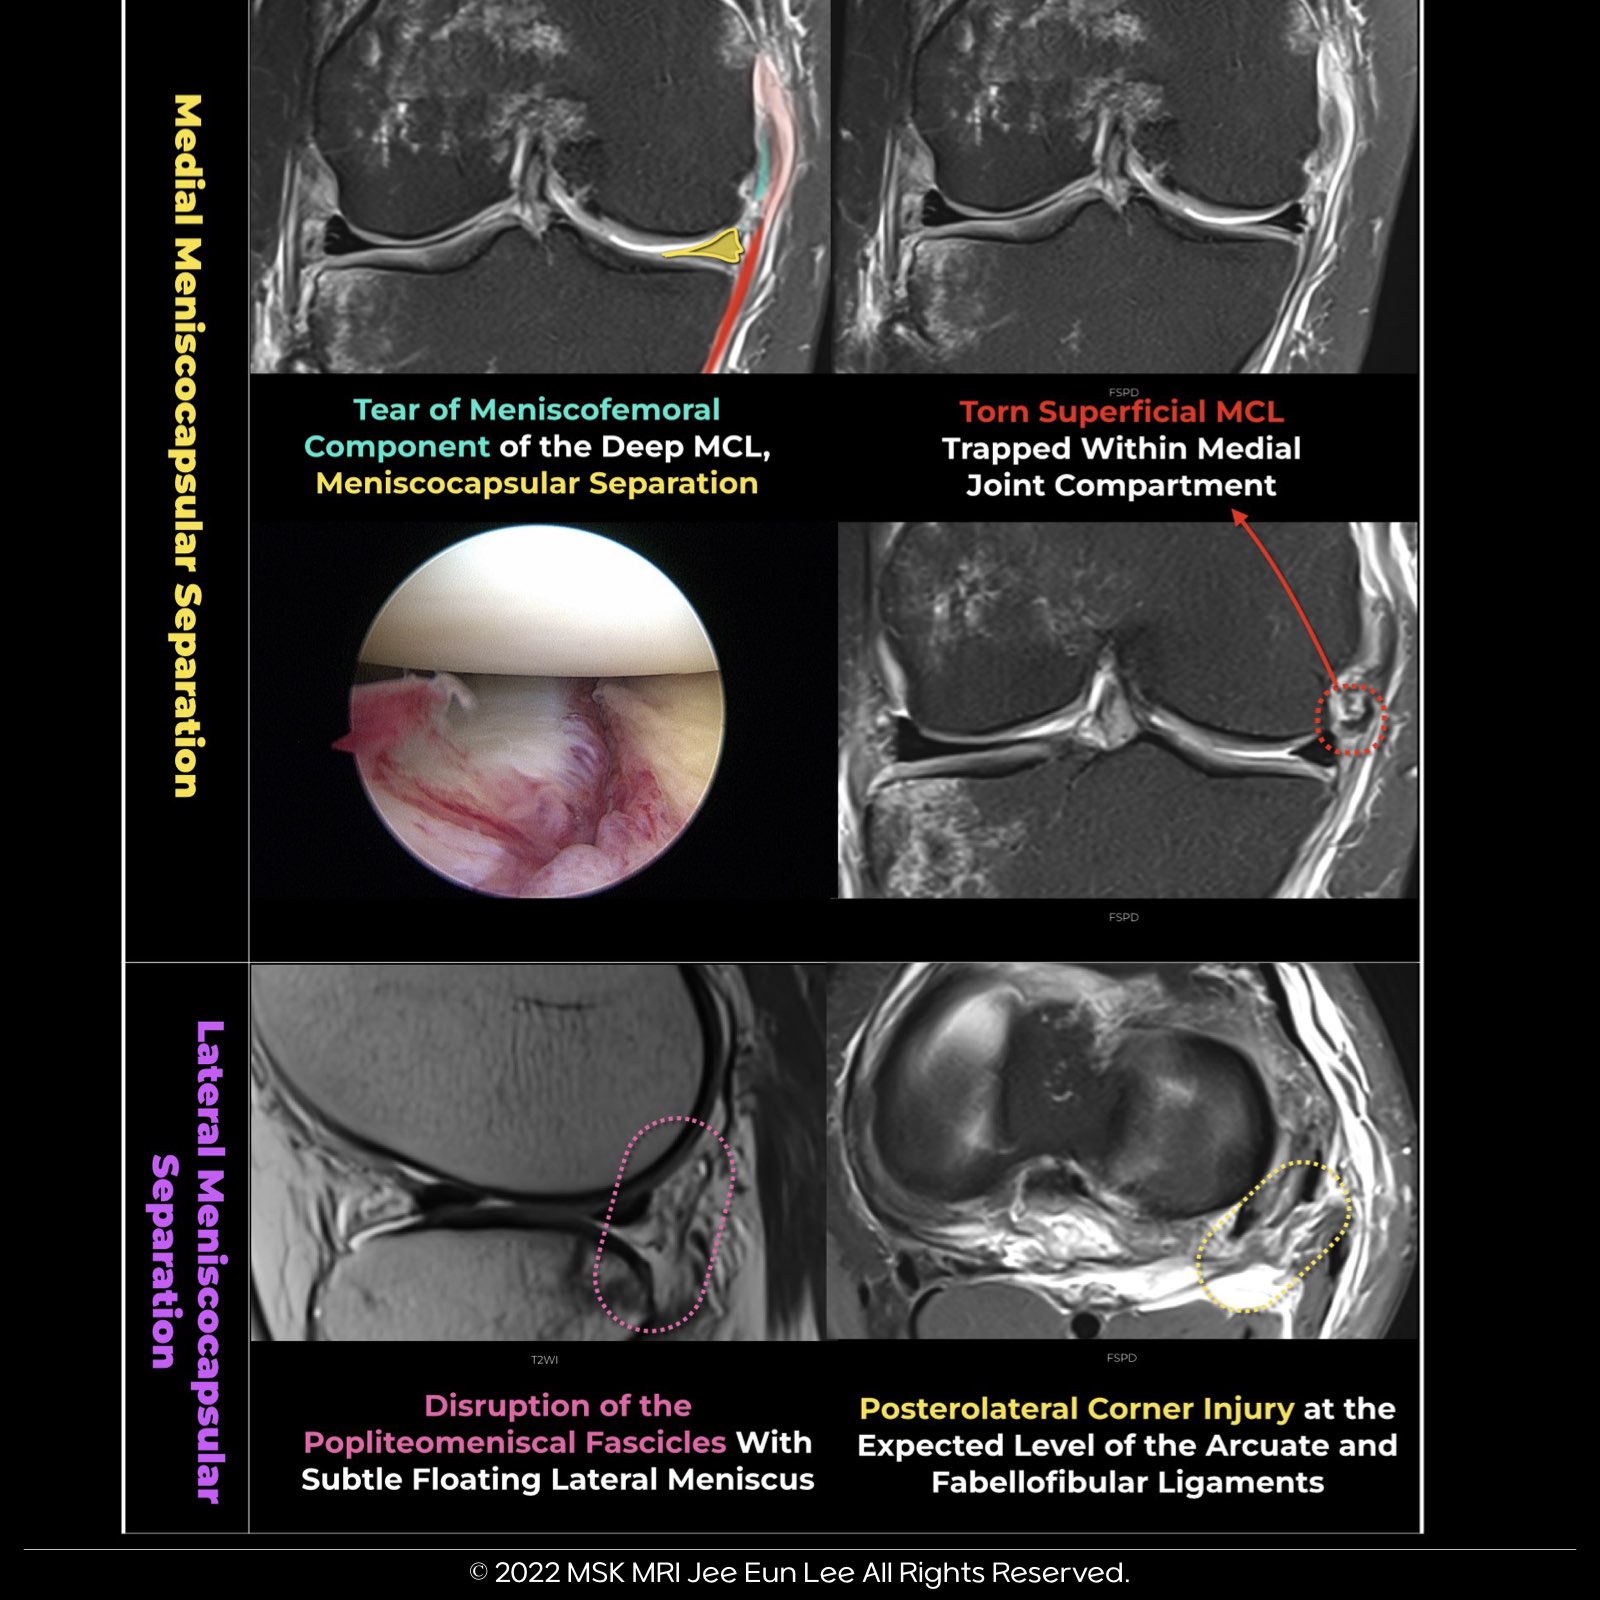

🔴 Meniscocapsular Separation

🔹Disruption of capsular attachment of meniscus, in trauma, with irregularity, and increased signal intensity within meniscofemoral or coronary ligament on T2WI.

🔹Tear of the supporting meniscotibial (coronary) or meniscofemoral ligaments typically at the attachment to the meniscus

🔹In comparison to the medial side, the lateral meniscus has a looser attachment to the lateral capsule. When fluid accumulates, these lateral attachments may expand outward, a condition that should not be mistaken for a tear.